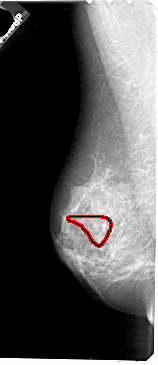

A_1723_1.LEFT_CC

LEFT_CC LINES 4201 PIXELS_PER_LINE 2026 BITS_PER_PIXEL 12 RESOLUTION 43.5 OVERLAY

FILE: A_1723_1.LEFT_CC.OVERLAY

TOTAL_ABNORMALITIES 1

ABNORMALITY 1

LESION_TYPE CALCIFICATION TYPE PLEOMORPHIC DISTRIBUTION SEGMENTAL

ASSESSMENT 4

SUBTLETY 3

PATHOLOGY MALIGNANT

TOTAL_OUTLINES 1

BOUNDARY